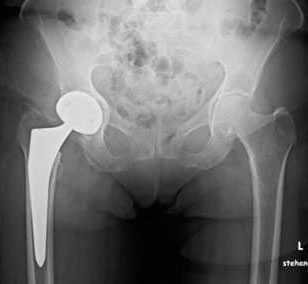

Рис.: Бесцементный тотальный эндопротез правого тазобедренного сустава, установленный в результате малоинвазивной операции по AMIS-технологии.

Бесцементный тотальный эндопротез правого тазобедренного сустава, установленный в результате малоинвазивной операции по AMIS-технологии.